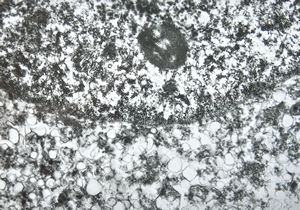

F,49y. | purulent meningitis- meningococcal v.s.

F,49y. | purulent meningitis- meningococcal v.s.

F,49y. | purulent meningitis- meningococcal v.s.